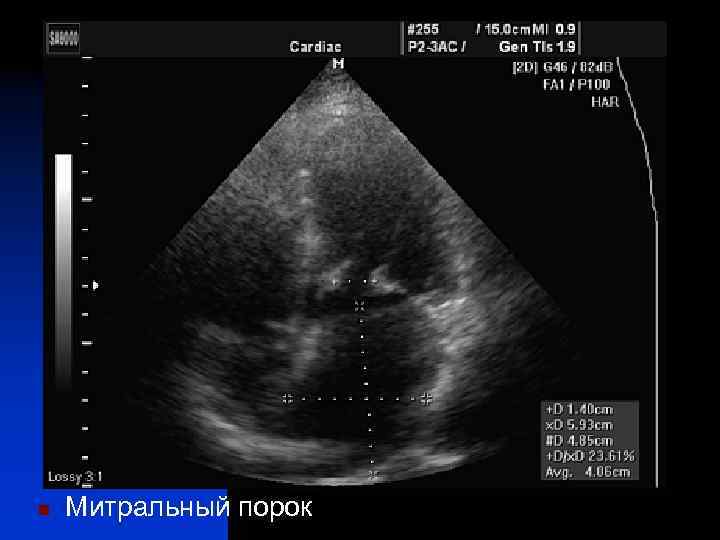

n Митральный порок

n Стеноз левого атрио-вентрикулярного отверстия